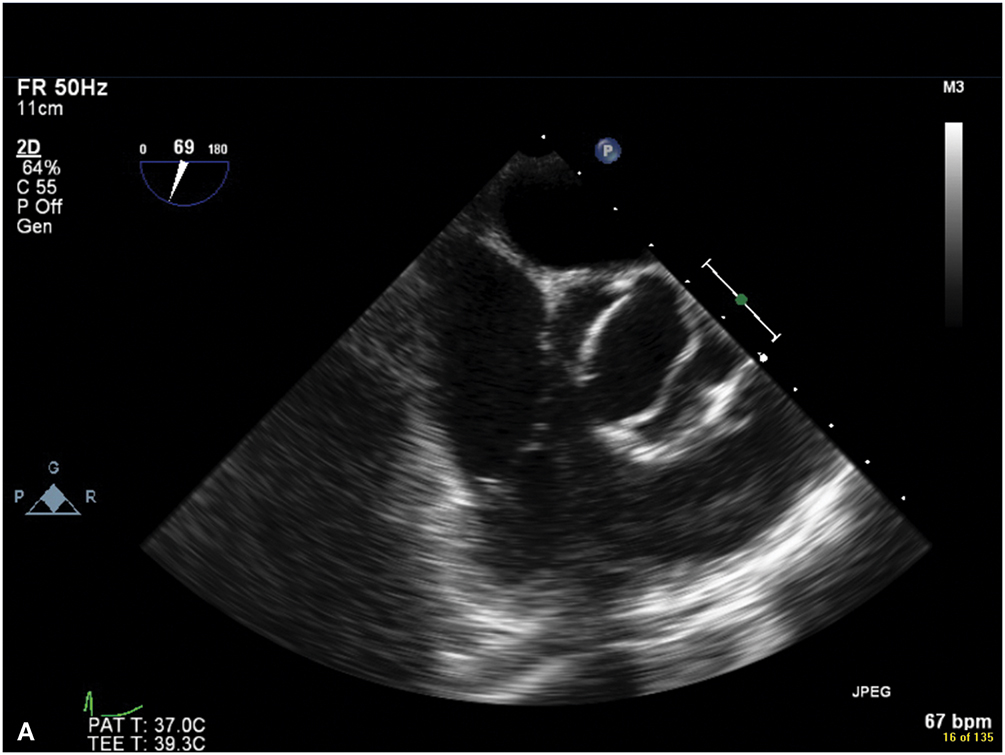

Figure 9.5.: A. Midesophageal Aortic Valve (Av) Short-Axis View on Transesophageal Echocardiography Showing a Bicuspid Valve, with the Fusion of the Left and Right Coronary Cusps.

A. Midesophageal aortic valve (AV) short-axis view on transesophageal echocardiography showing a bicuspid valve, with the fusion of the left and right coronary cusps. B. Midesophageal aortic valve long-axis view on transesophageal echocardiography demonstrating the characteristic doming of a stenotic bicuspid AV and blunting of the sinotubular junction due to aortic root (ascending aortic) dilatation.